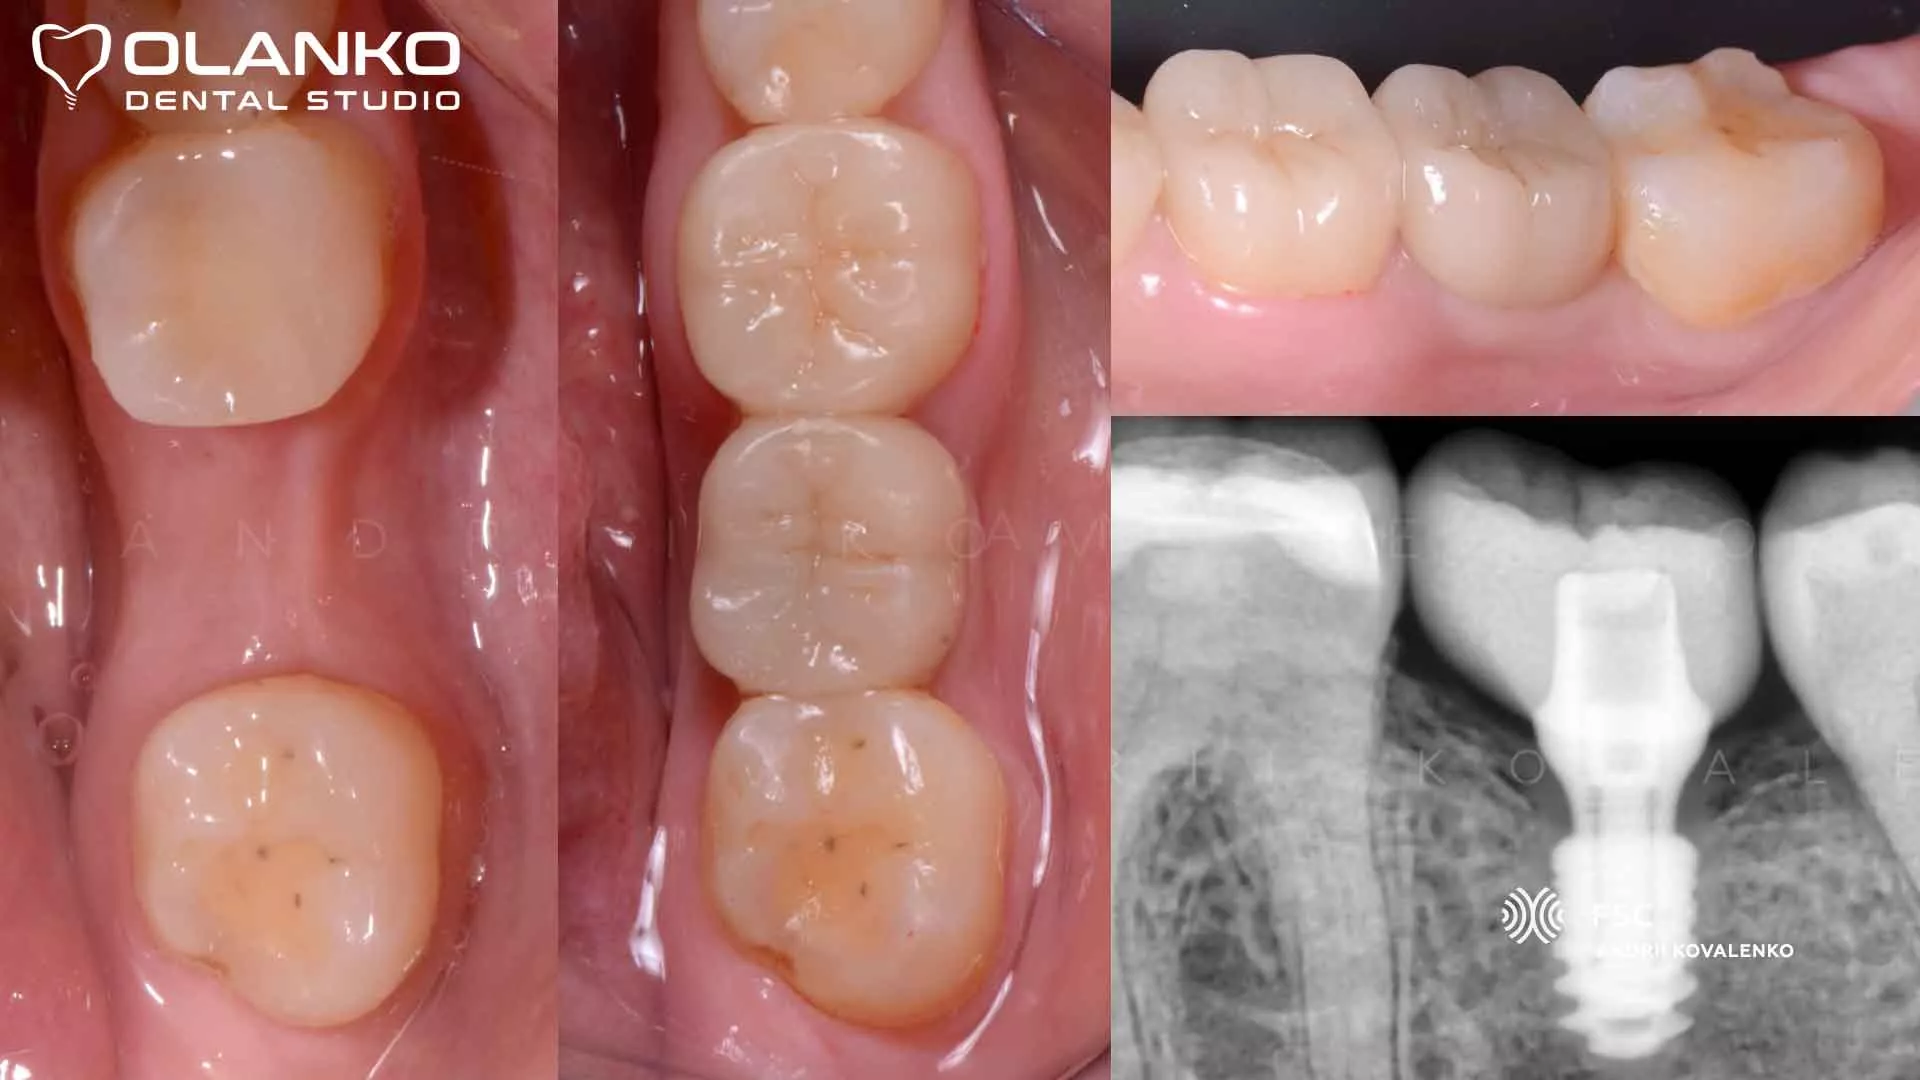

Мостовидний протез чи імплант - що краще?

Міст або імплант: що краще вибрати?

У житті багатьох людей зустрічаються ситуації, коли відбувається втрата зубів. Відсутність зубів у роті не тільки псує естетичний зовнішній вигляд посмішки, але і доставляє великий дискомфорт пацієнту. Щоб повернути привабливу посмішку, а також відновити жувальні функції щелепи, можна звернутися до процесів протезування. Сучасні стоматологічні методи дозволяють здійснити різні варіанти протезування зубів з урахуванням побажань клієнта. Проте, багато людей не можуть вирішити що краще вибрати: зубний міст або імплант.

Установка імплантів, як процес протезування зубів

Імплантанти - це найбільш сучасний і надійний метод для того, щоб замінити втрачені зуби.

Імплантант включає в себе три основні елементи, а саме коронку, абатмент і штучний корінь. Імплантація показана в наступних випадках: